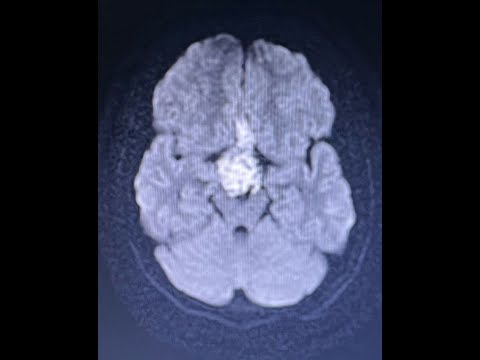

Hellow guys, Welcome to my website, and you are watching D11 D12 NEUROFIBROMA-DR LAXMIKANT BHOPLE/DR SANDEEP GORE SHREE GANGA HOSPITAL NANDED. and this vIdeo is uploaded by Dr. Laxmikant Bhople NeuroCare at 2024-07-24T04:56:42-07:00. We are pramote this video only for entertainment and educational perpose only. So, I hop you like our website.